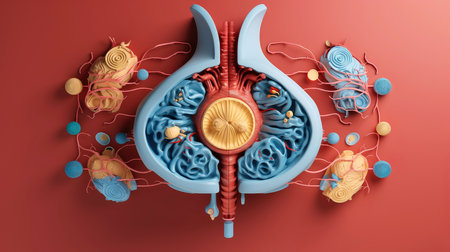

Immune system attacking kidneys with cells illustrating autoimmune disease concept in vivid digital artwork. concept of medical illustration, kidney health, immune response.

A close up of a plant organ with blue and red colors. The organ is surrounded by a white background